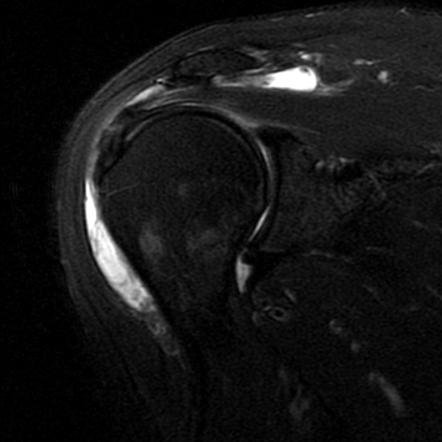

Imaging such as X-rays may be used to check for bone spurs or structural narrowing. Ultrasound or MRI can help confirm inflammation of the bursa, detect fluid buildup, and identify any coexisting rotator cuff tears.